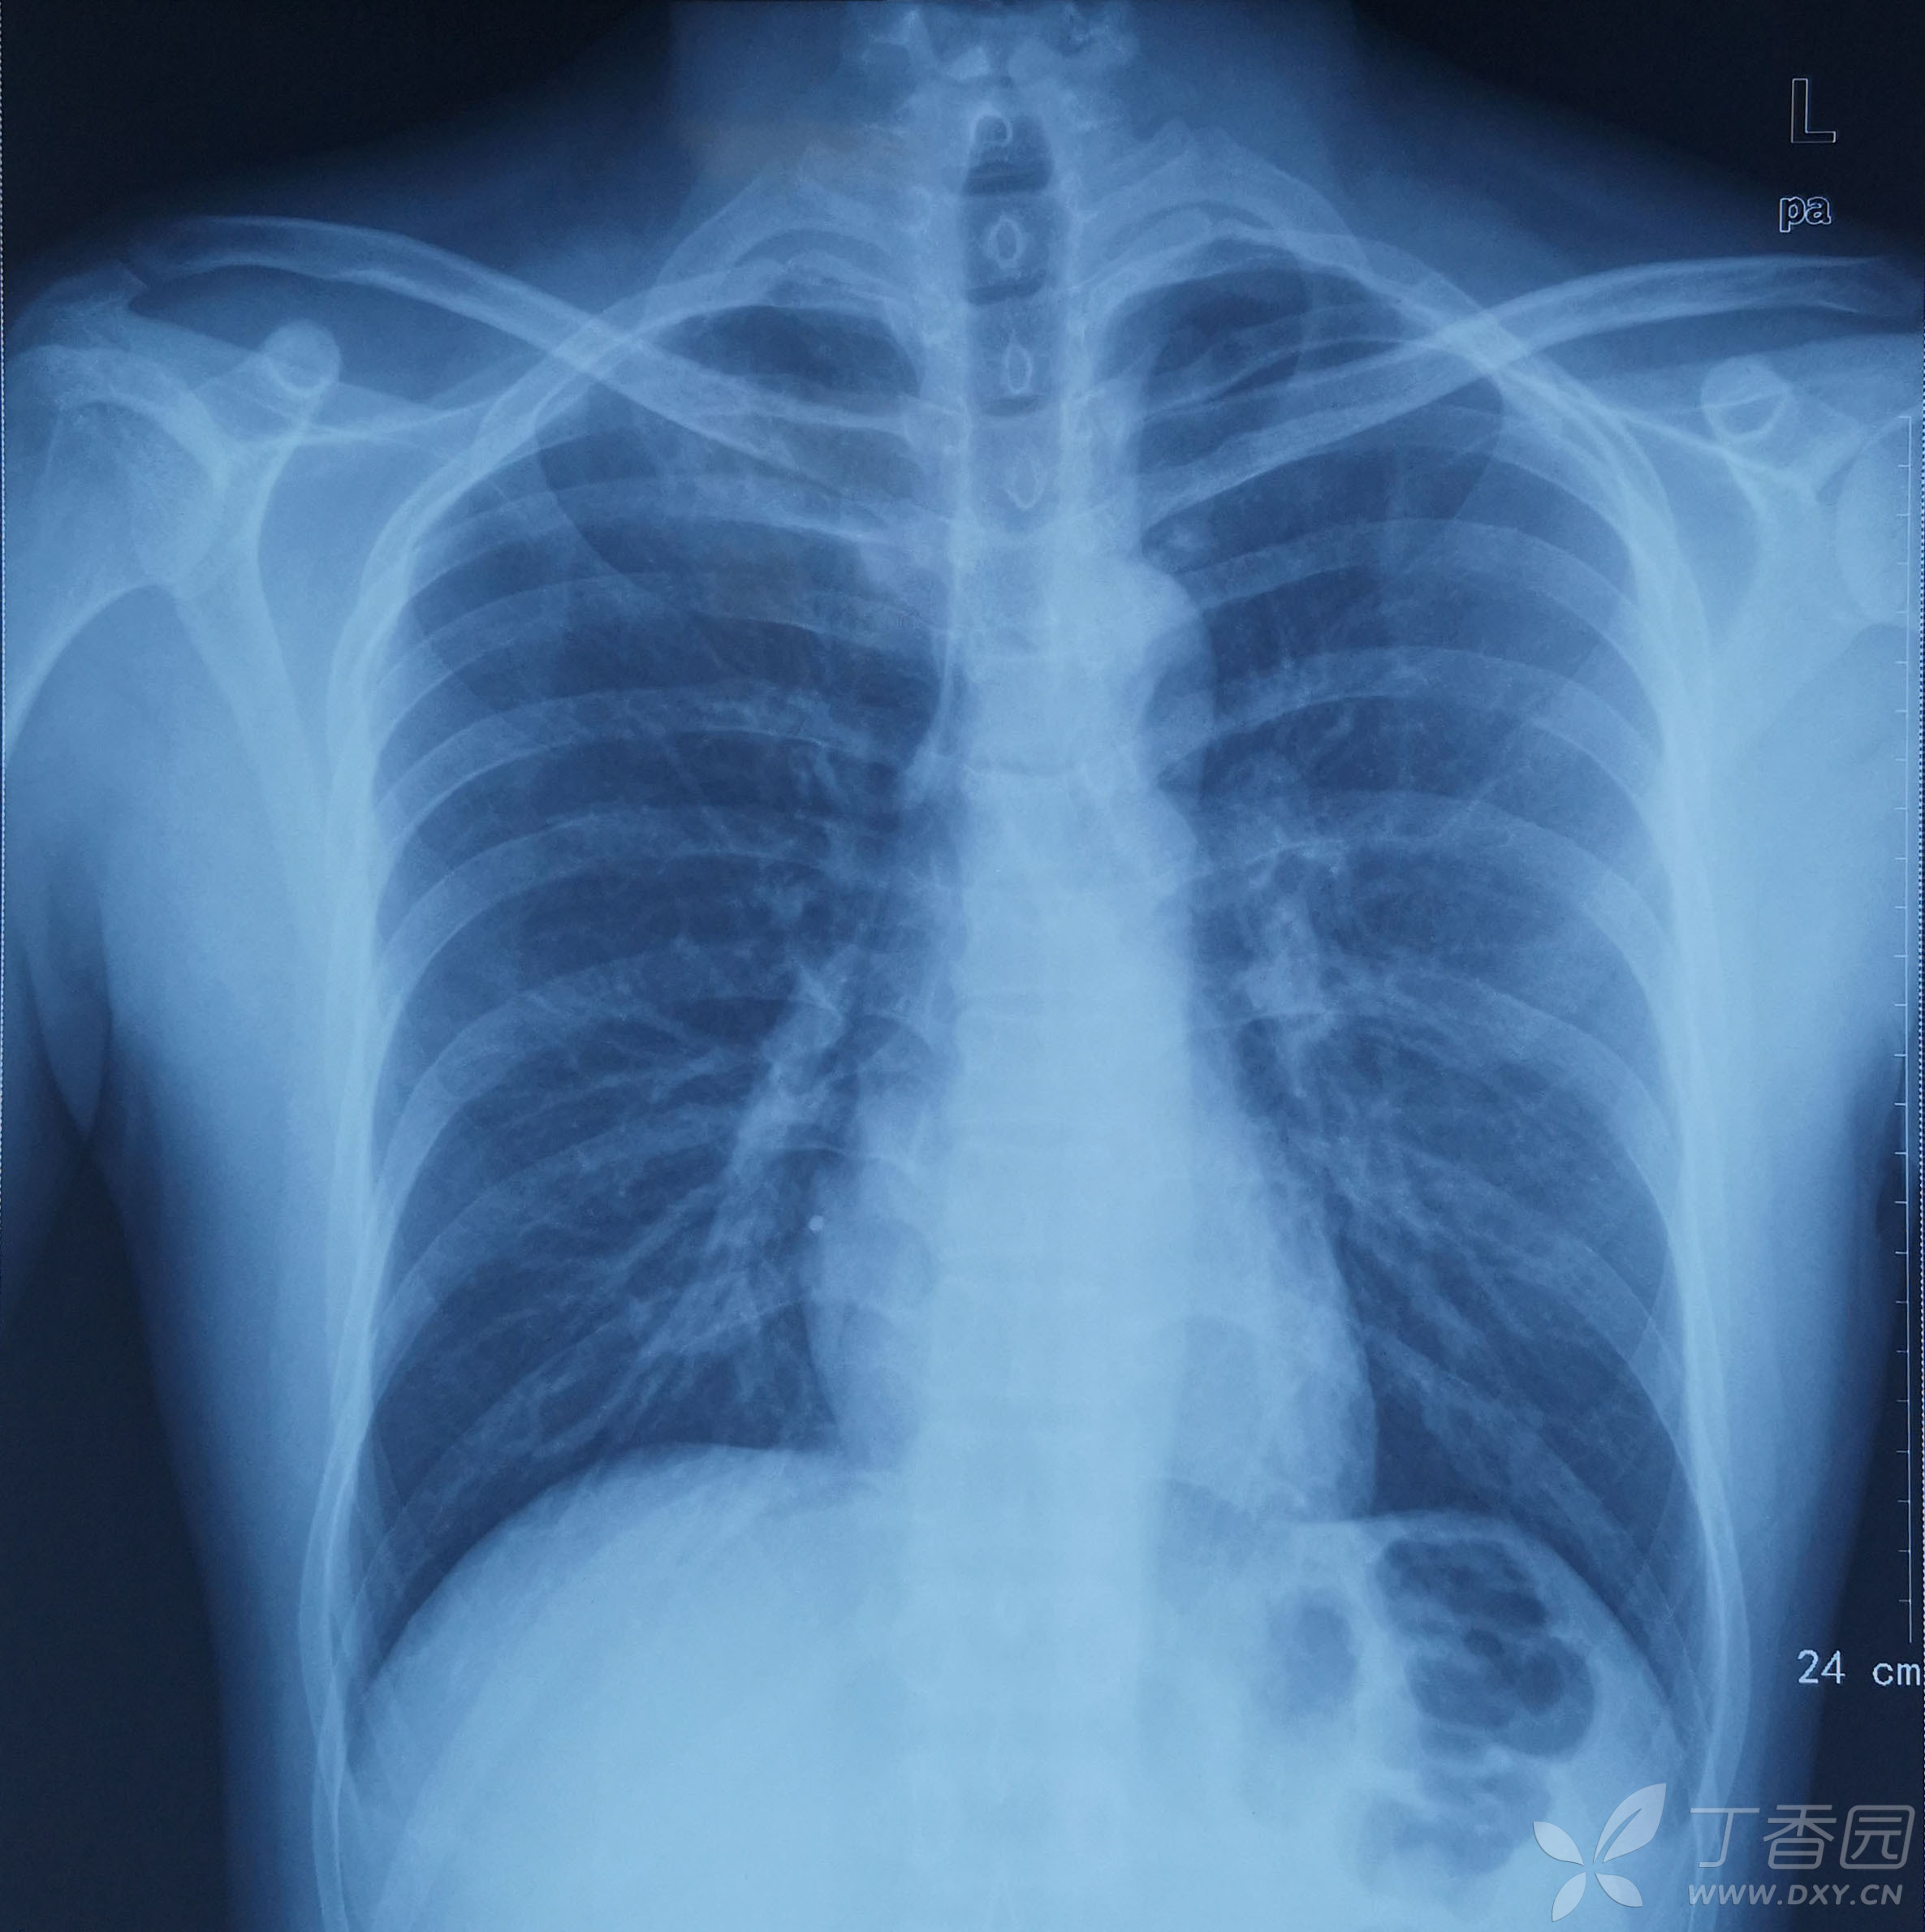

今天的一个病例肋骨分叉

图片尺寸1823x1617